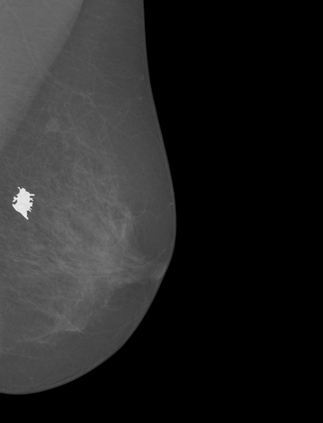

Breast cancer is the most widespread neoplasm among women and early detection of this disease is critical. Deep learning techniques have become of great interest to improve diagnostic performance. Nonetheless, discriminating between malignant and benign masses from whole mammograms remains challenging due to them being almost identical to an untrained eye and the region of interest (ROI) occupying a minuscule portion of the entire image. In this paper, we propose a framework, parameterized hypercomplex attention maps (PHAM), to overcome these problems. Specifically, we deploy an augmentation step based on computing attention maps. Then, the attention maps are used to condition the classification step by constructing a multi-dimensional input comprised of the original breast cancer image and the corresponding attention map. In this step, a parameterized hypercomplex neural network (PHNN) is employed to perform breast cancer classification. The framework offers two main advantages. First, attention maps provide critical information regarding the ROI and allow the neural model to concentrate on it. Second, the hypercomplex architecture has the ability to model local relations between input dimensions thanks to hypercomplex algebra rules, thus properly exploiting the information provided by the attention map. We demonstrate the efficacy of the proposed framework on both mammography images as well as histopathological ones, surpassing attention-based state-of-the-art networks and the real-valued counterpart of our method. The code of our work is available at https://github.com/elelo22/AttentionBCS.